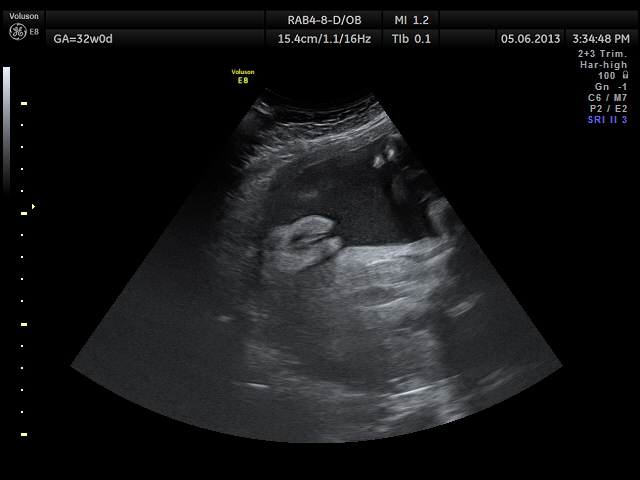

сложно спутать)))) ну эо напши 32 недели, но на 24, и на 16 выглядело также почти)